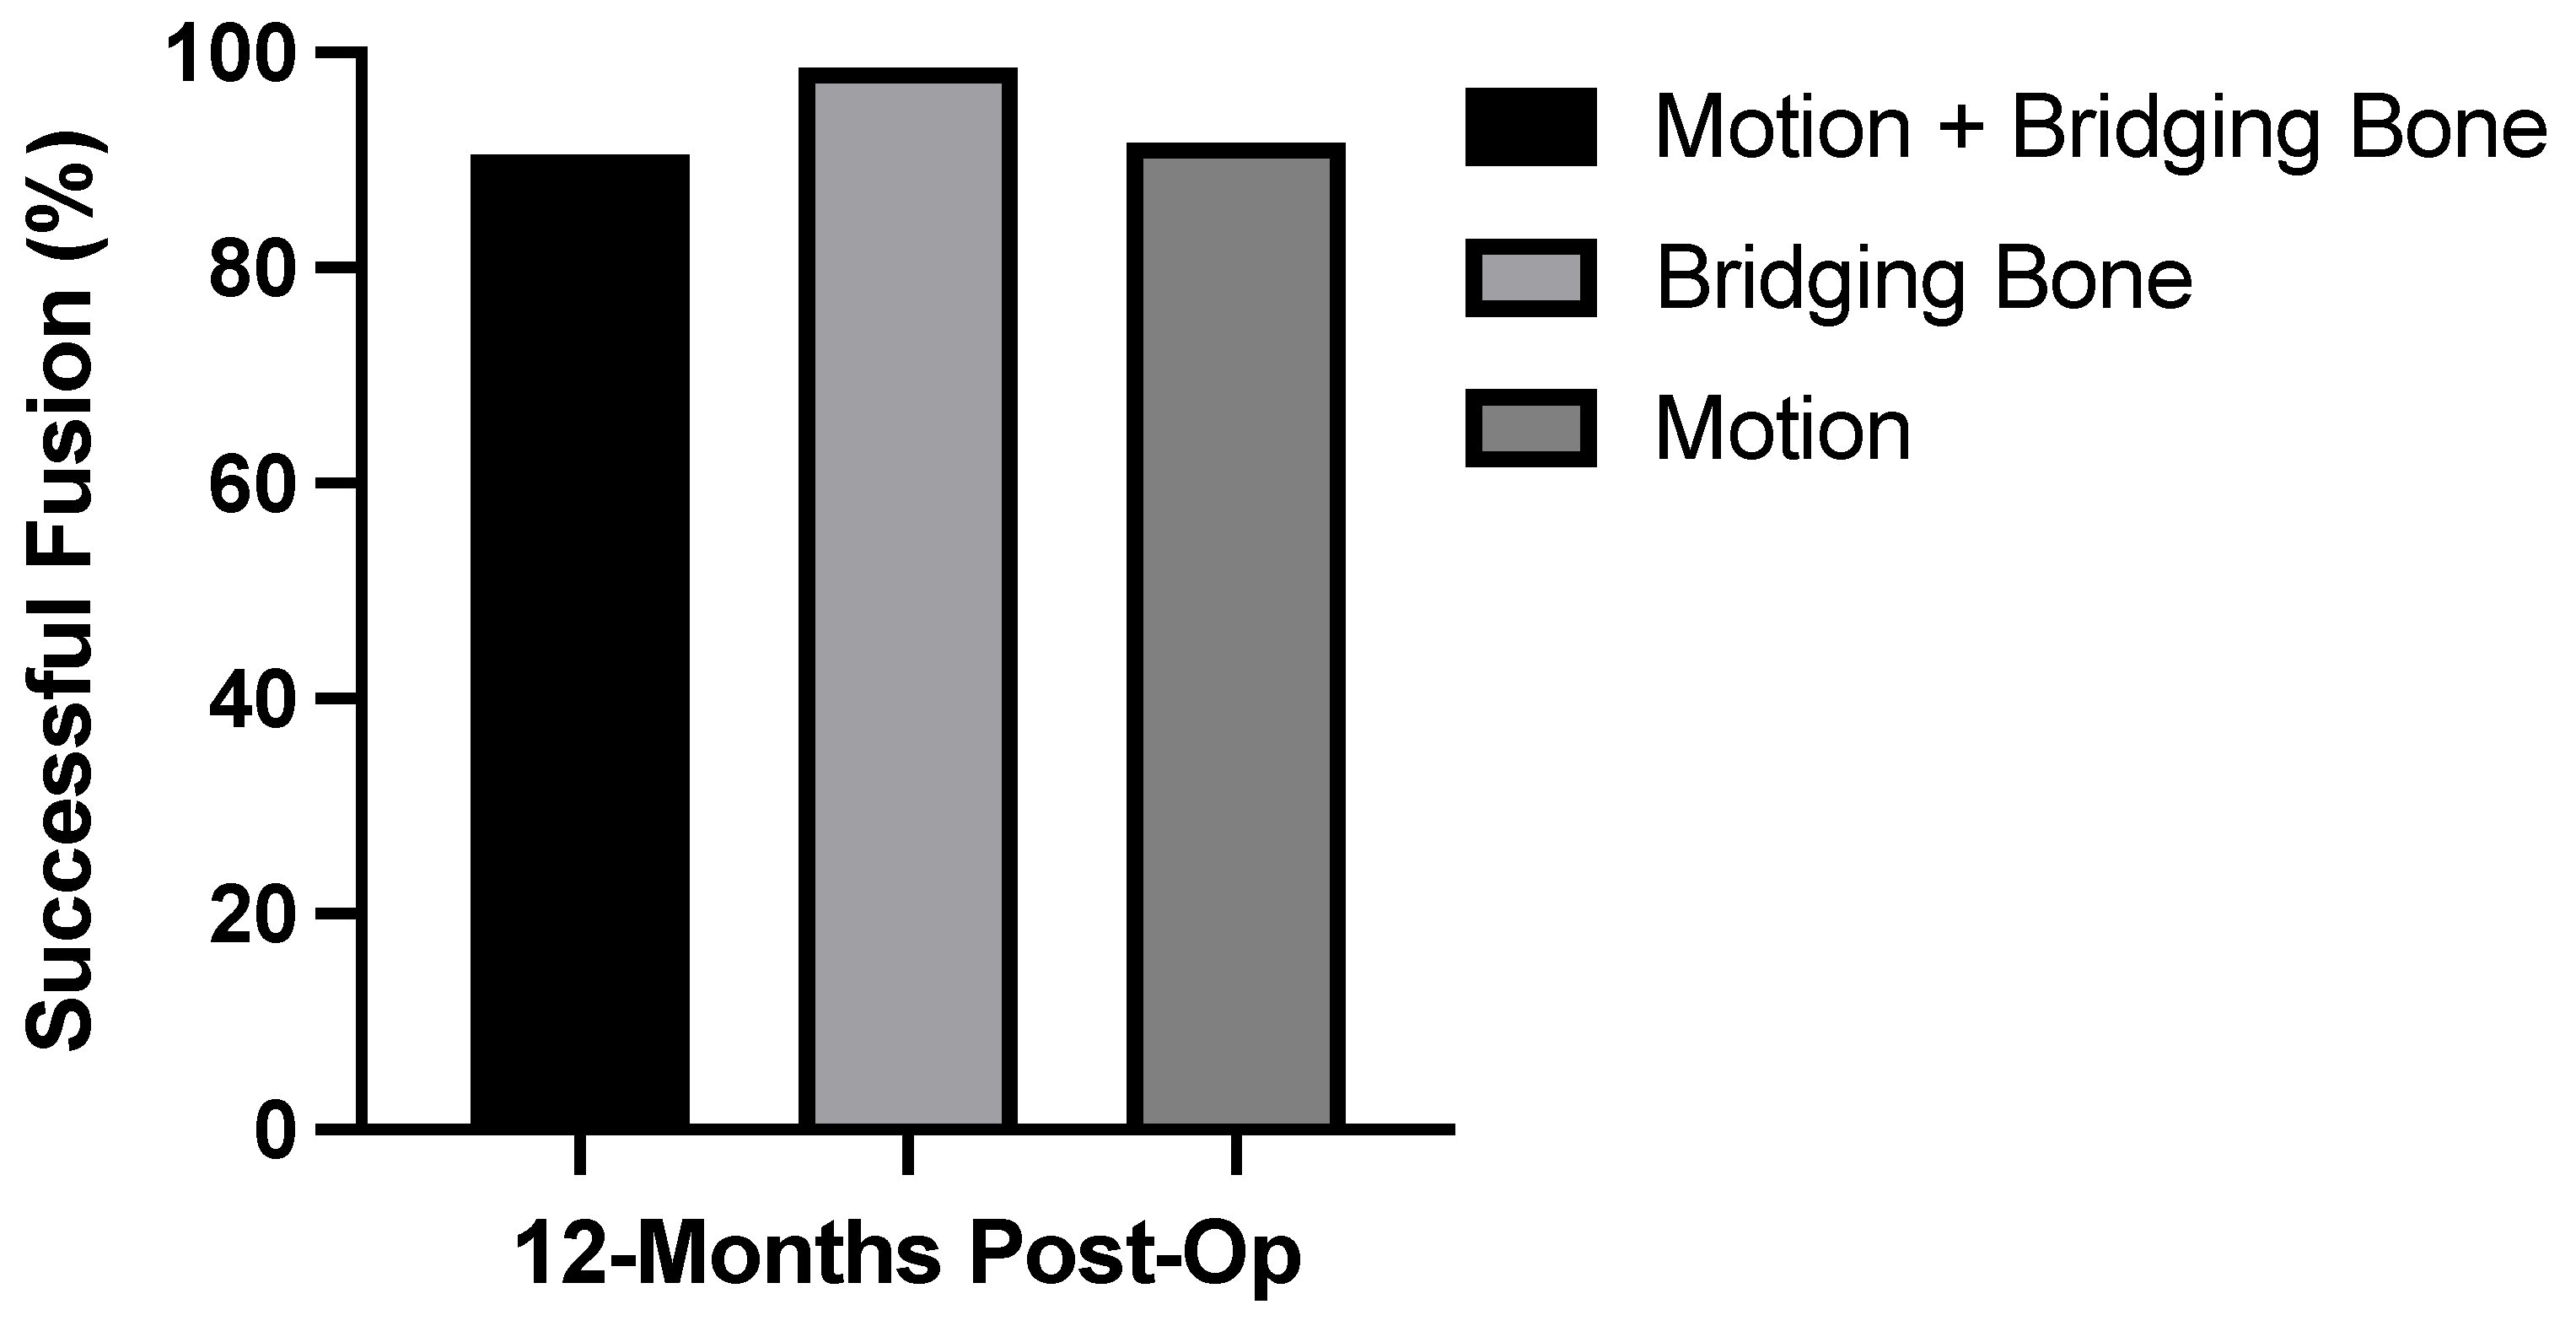

3.2. Radiographic Fusion Outcomes